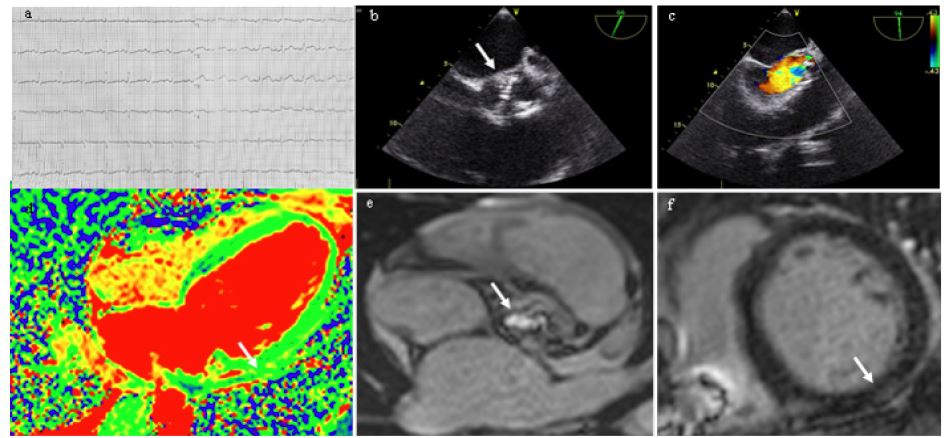

ECG showed sinus tachycardia (Figure 2a), 24-hour ECG monitoring revealed no significant rhythm abnormalities. EchoCG visualized dilated left chambers (LV EDD 6.4 cm, 3.72 cm/m2, EDV 204 ml, ESV 136 ml, left atrium 78 ml), systolic function dramatically decreased (EF 25%, VTI 14 cm, dp/dt 909 mmHg), sPAP 40 mmHg. The Transesophageal EchoCG revealed a 0.3 × 0.5 cm echopositive mobile mass in the right commissure area (Figure 2b), bicuspid valve cusps were thickened, aortic stenosis (aortic orifice area 1.1 cm2, AV velocity 441 cm/s, maximum and mean gradients 77 and 42 mmHg.) was combined with grade II aortic regurgitation (Figure 2c).

Blood culture was negative, but procalcitonin level were significantly increased (1.94 ng/ml, normal less than 0.07 ng/ml). On the basis of one major and at least 4 minor criteria, bicuspid AV IE was diagnosed. Antibiotic therapy with vancomycin 2 g/day and ceftriaxone 2 g/day, intravenous infusion of 50 g immunoglobulin were performed for 4 weeks. Body temperature and procalcitonin levels normalized. At the same time there was evidence of myocarditis: elevated anti-heart antibodies levels (1:160-1:320), signs of myocardial oedema and subepicardial delayed accumulation on MRI (Figure 2g).

Figure 1: Results of instrumental investigations. (a) - ECG, paper speed 25 mm/sec: sinus tachycardia; b, c - EchoCG: vegetation on the aortic bicuspid valve cusp (b), aortic regurgitation (c); d-f - Contrast enhanced cardiac MRI: LV lateral wall edema, T2, arrow (d); marked aortic orifice narrowing, arrow (e); subepicardial LGE along the LV posterior segment at basal level with spreading to the middle segment, arrow (f).